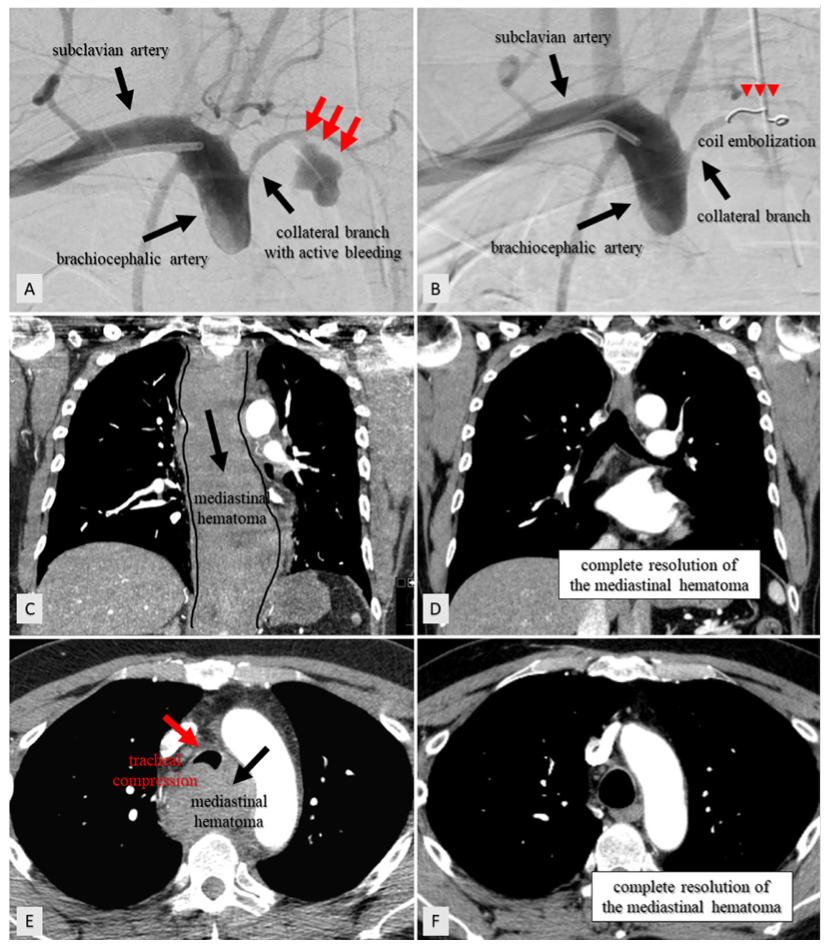

A 65-year-old man who presented with lateral ST-segment-elevation myocardial infarction was referred for primary percutaneous coronary intervention. J-wire and 5.2-Fr JR4 diagnostic catheter progression through right radial artery access was hampered by radial artery spasm and subclavian artery tortuosity. Then, a hydrophilic-coated guidewire was used to assist catheter advancement into the aortic root. Coronary angiography revealed an acute occlusion of the first obtuse marginal artery, which was successfully revascularized with 2 consecutive drug-eluting stents (Video Series). Three hours later, the patient developed symptoms of pleuritic chest pain, dyspnea, stridor, and evolved with shock. Thoracic computed tomography (CT) angiography revealed a large mediastinal hematoma compressing the airway (Figures 1C, 1E and Figure 2). Due to high index of suspicion and after multidisciplinary heart team discussion, an upper limb angiography was performed, which detected perforation of a small collateral branch of the brachiocephalic artery (Figure 1A). The perforation was treated with a single coil embolization, resolving the active bleeding (Figure 1B and Figure 3). Control CT imaging at 2-month follow-up revealed complete resolution of the mediastinal hematoma and airway compression (Figures 1D, 1F).

This clinical case illustrates an extremely rare and lethal complication of radial access PCI. We suspect the perforation was probably caused by the hydrophilic-coated guidewire. Mediastinal hematoma has scarcely been reported in the literature and, when present, the exact location of the bleeding was rarely identified. Rapid identification through chest imaging is crucial. In critically ill patients, endovascular management with coil embolization offers a less invasive and faster alternative to covered-stent implantation or surgery.